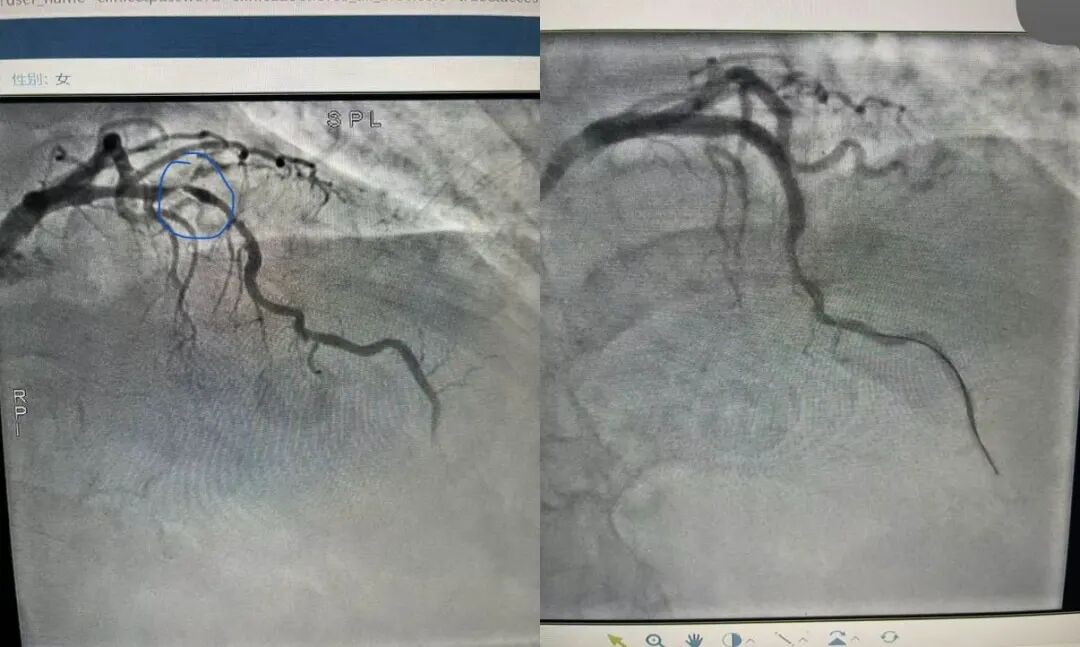

当患者生命体平稳后,医护人员立即将其转运至导管室。冠脉造影结果清晰显示,患者主要供血血管存在高度狭窄,局部几近闭塞——这正是诱发此次致命心律失常的直接“元凶”。

心内科介入团队凭借丰富的临床经验和娴熟的操作技巧,立即为患者实施急诊经皮冠状动脉介入治疗(PCI),成功植入1枚冠脉支架,快速开通闭塞血管,恢复心肌有效供血,从根源上遏制了心律失常的再次发作。